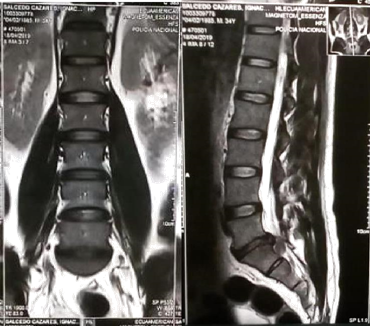

Physical examination: Inability to walk heel-to-toe, no spinal deformities were observed, lumbar paravertebral muscles were palpated, contracted and slightly painful, Steindler L5-S1 +, Lasegue + at 15° left, left Bragard +, left achilles hyporeflexia, left L5-S1 dermatoma hyposthesia, FM 3/5 left lower extremity.9,10 Complementary examinations were performed including MRI in which a left paracentral foraminal protrusion type hernia with calcification type morphological changes and with caudal migration L5-S1, in addition to a severe narrowing of the canal (Figure 1 & 2).11–15

Figure 1 Axial MRI of L5, herniation is observed.

Figure 2 MRI of lumbar spine A) AP view; B) lateral view: L5-S1 herniation is identified.